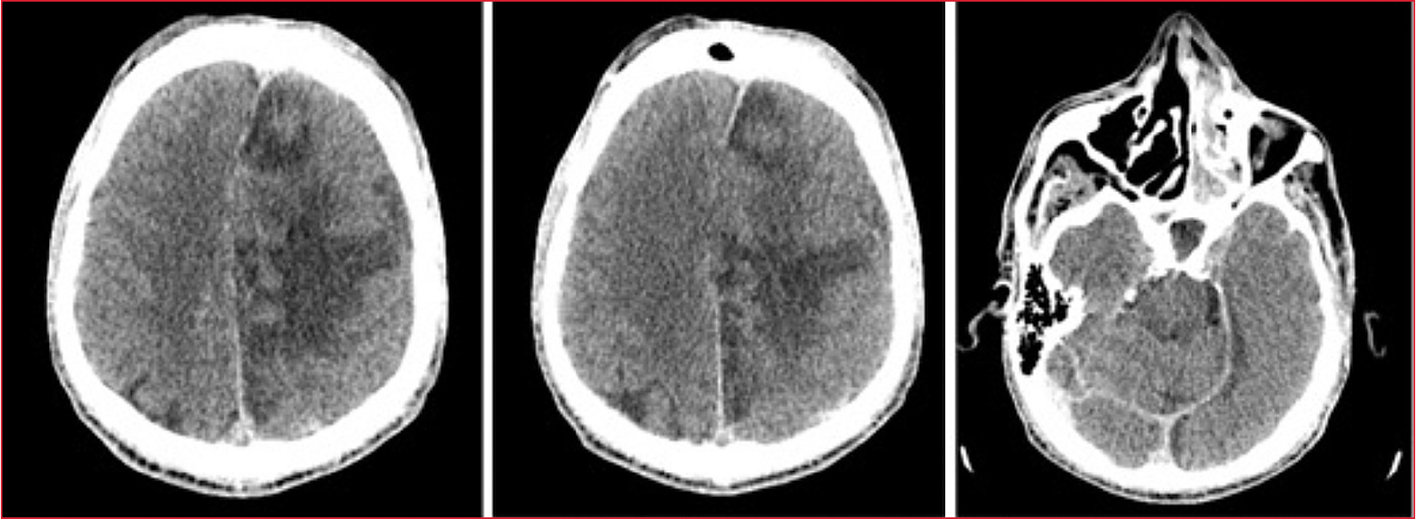

La tomografía computarizada de cráneo mostró una lesión isquémica subaguda en el territorio de la arteria cerebral anterior izquierda con áreas de infarto establecido, así como sinusopatía frontal izquierda crónica con absceso subperióstico intra y extracerebral asociado (Figura 1).

Figura 1. Lesión isquémica subaguda en el

territorio de la arteria cerebral anterior izquierda. Áreas de infarto

establecido y sinusopatía frontal izquierda crónica con absceso subperióstico

intra y extracerebral asociado.